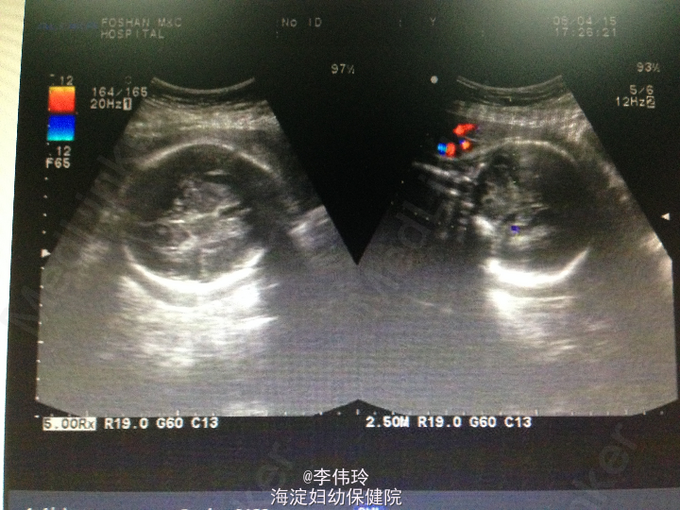

孕妇因停经29周,不规则下腹胀2小时入院。自然流产1次。OGTT 5.36-9.04-7.63mmol/L,确诊为妊娠期糖尿病,

查体:生命体征平稳,心肺未见明显异常。双下肢无水肿。 辅查:B超:活单胎,头位,相当孕29+周,羊水量未见异常。胎盘成熟度0+度,脐带绕颈1周未除,BPS8分,S/D2.86。宫颈长约2.7cm,宫颈内口未见扩张。血HCG 96g/L。白带分析:真菌(+)